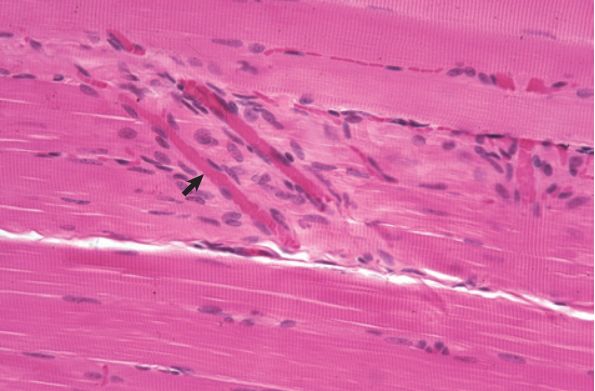

76.在鏡檢蘇木紫與伊紅染色的肌肉組織切片,所看到的橫紋為下列何構造?

(A)I band

(B)A band

(C)M line

(D)Z line

橫紋為粗、細肌絲重疊造成。詳見 http...

A bands (dark lines)...